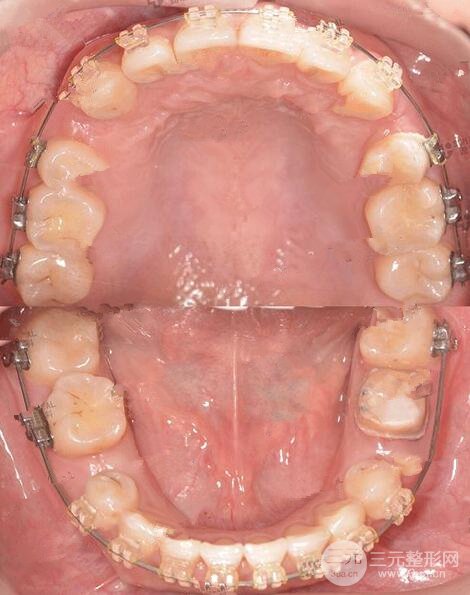

北京大學口腔醫(yī)院:我的牙齒術(shù)前牙列不齊上中線偏斜,尖牙扭轉(zhuǎn) 笑起來就是一顆小虎牙露在外面。醫(yī)生根據(jù)我的情況,給我做了詳細的緩解計劃。

這是拔除四顆雙尖牙后 原本不對稱的牙弓現(xiàn)在已經(jīng)對稱 中線也調(diào)整到正常位置

現(xiàn)在還在排齊階段拔牙間隙已經(jīng)變小很多,后期我們繼續(xù)整平牙弓,就可以完全關(guān)閉拔牙間隙調(diào)整咬合了,我的左下第(一)恒磨牙是做過根管緩解的,現(xiàn)在在重新制作臨時牙套,再繼續(xù)正畸緩解。